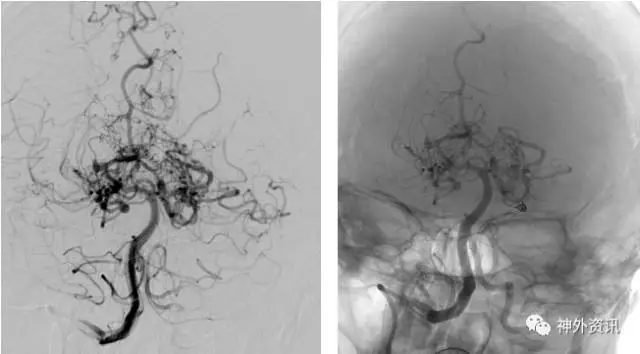

(3D血管融合:左侧额颞顶部巨大AVM,大小约10.4*6.7*5.7cm)

(治疗中,ENVOY DA导引导管置于左侧大脑前动脉A1段)

(SONIC 导管顺利超选至畸形血管巢,并且拔管顺利)